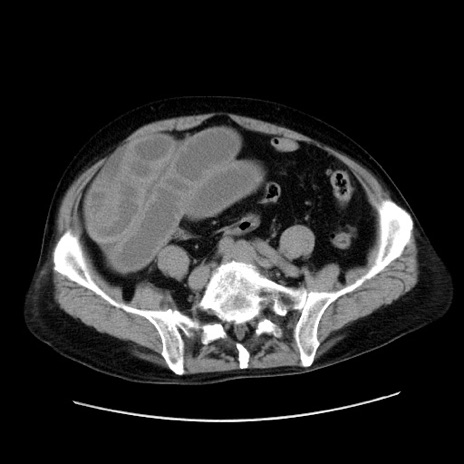

症例30(横断像)

【症例】80歳代男性

【主訴】臍周囲痛

【現病歴】約6時間前から臍下部痛が出現。次第に腹部膨隆・背部痛も生じてきたため来院。背部痛の場所は変化しない。

【身体所見】意識清明、BT 36.3℃、BP  131/87mmHg、P 87bpm、SpO2 100%(RA)、臍周囲自発痛・圧痛あり、反跳痛なし、自発痛部位に一致して板状硬あり、腹部膨隆、腸雑音減弱、CVA tenderness両側陰性。

【データ】WBC 19600、CRP 0.33

冠状断像